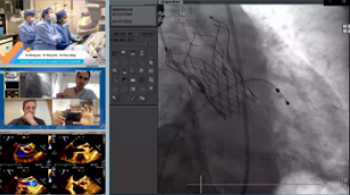

• 参加线上国际学术研讨(含手术直播)